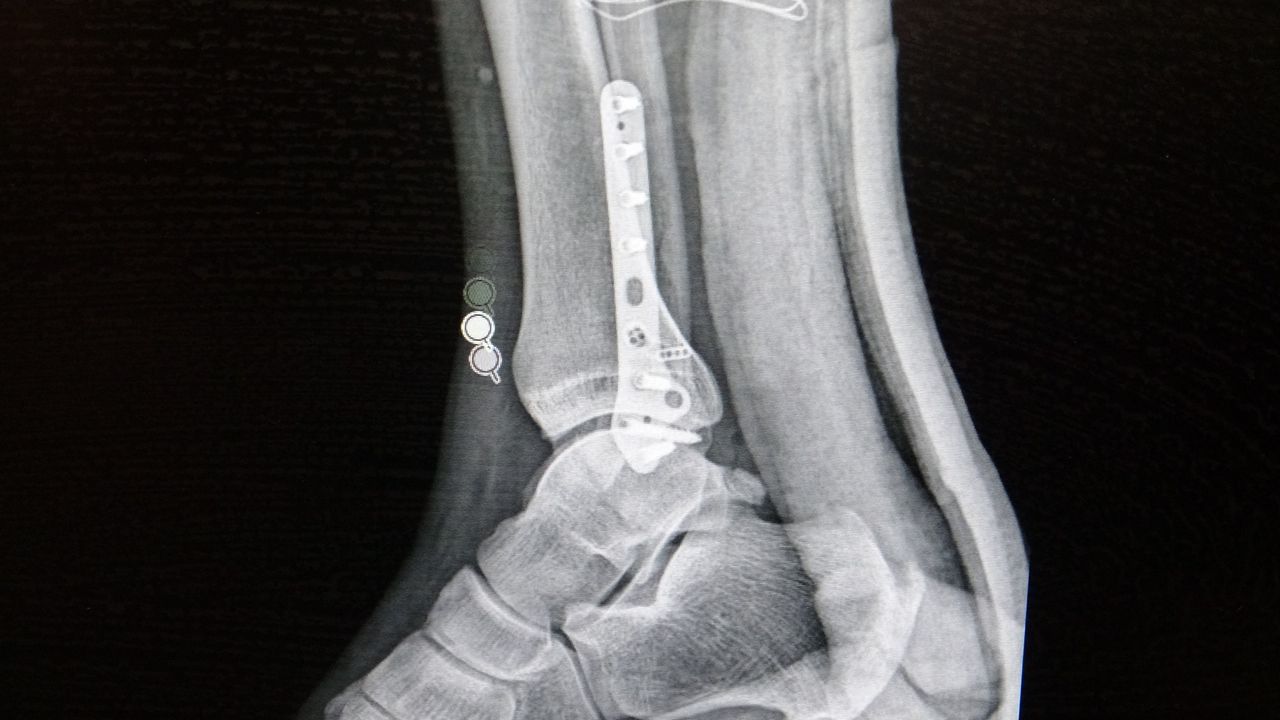

Ortopedi polikliniklerine en sık ayak bileği, diz ve omuz yaralanmalarıyla başvurulduğunu belirten Demirbaş, futbol nedeniyle yaralanma oranlarının da ilk sırada yer aldığını söyledi. Konuya ilişkin Demirbaş, "Futbolda menisküs yırtıkları, ön çapraz bağ yırtıkları, iç ve dış yan bağ yaralanmaları, aşil tendon kopmaları ve ayak bileği bağ yaralanmaları çok sık görülüyor. Ayrıca spora bağlı kırıklar da önemli bir yer tutuyor" ifadelerini kullandı.